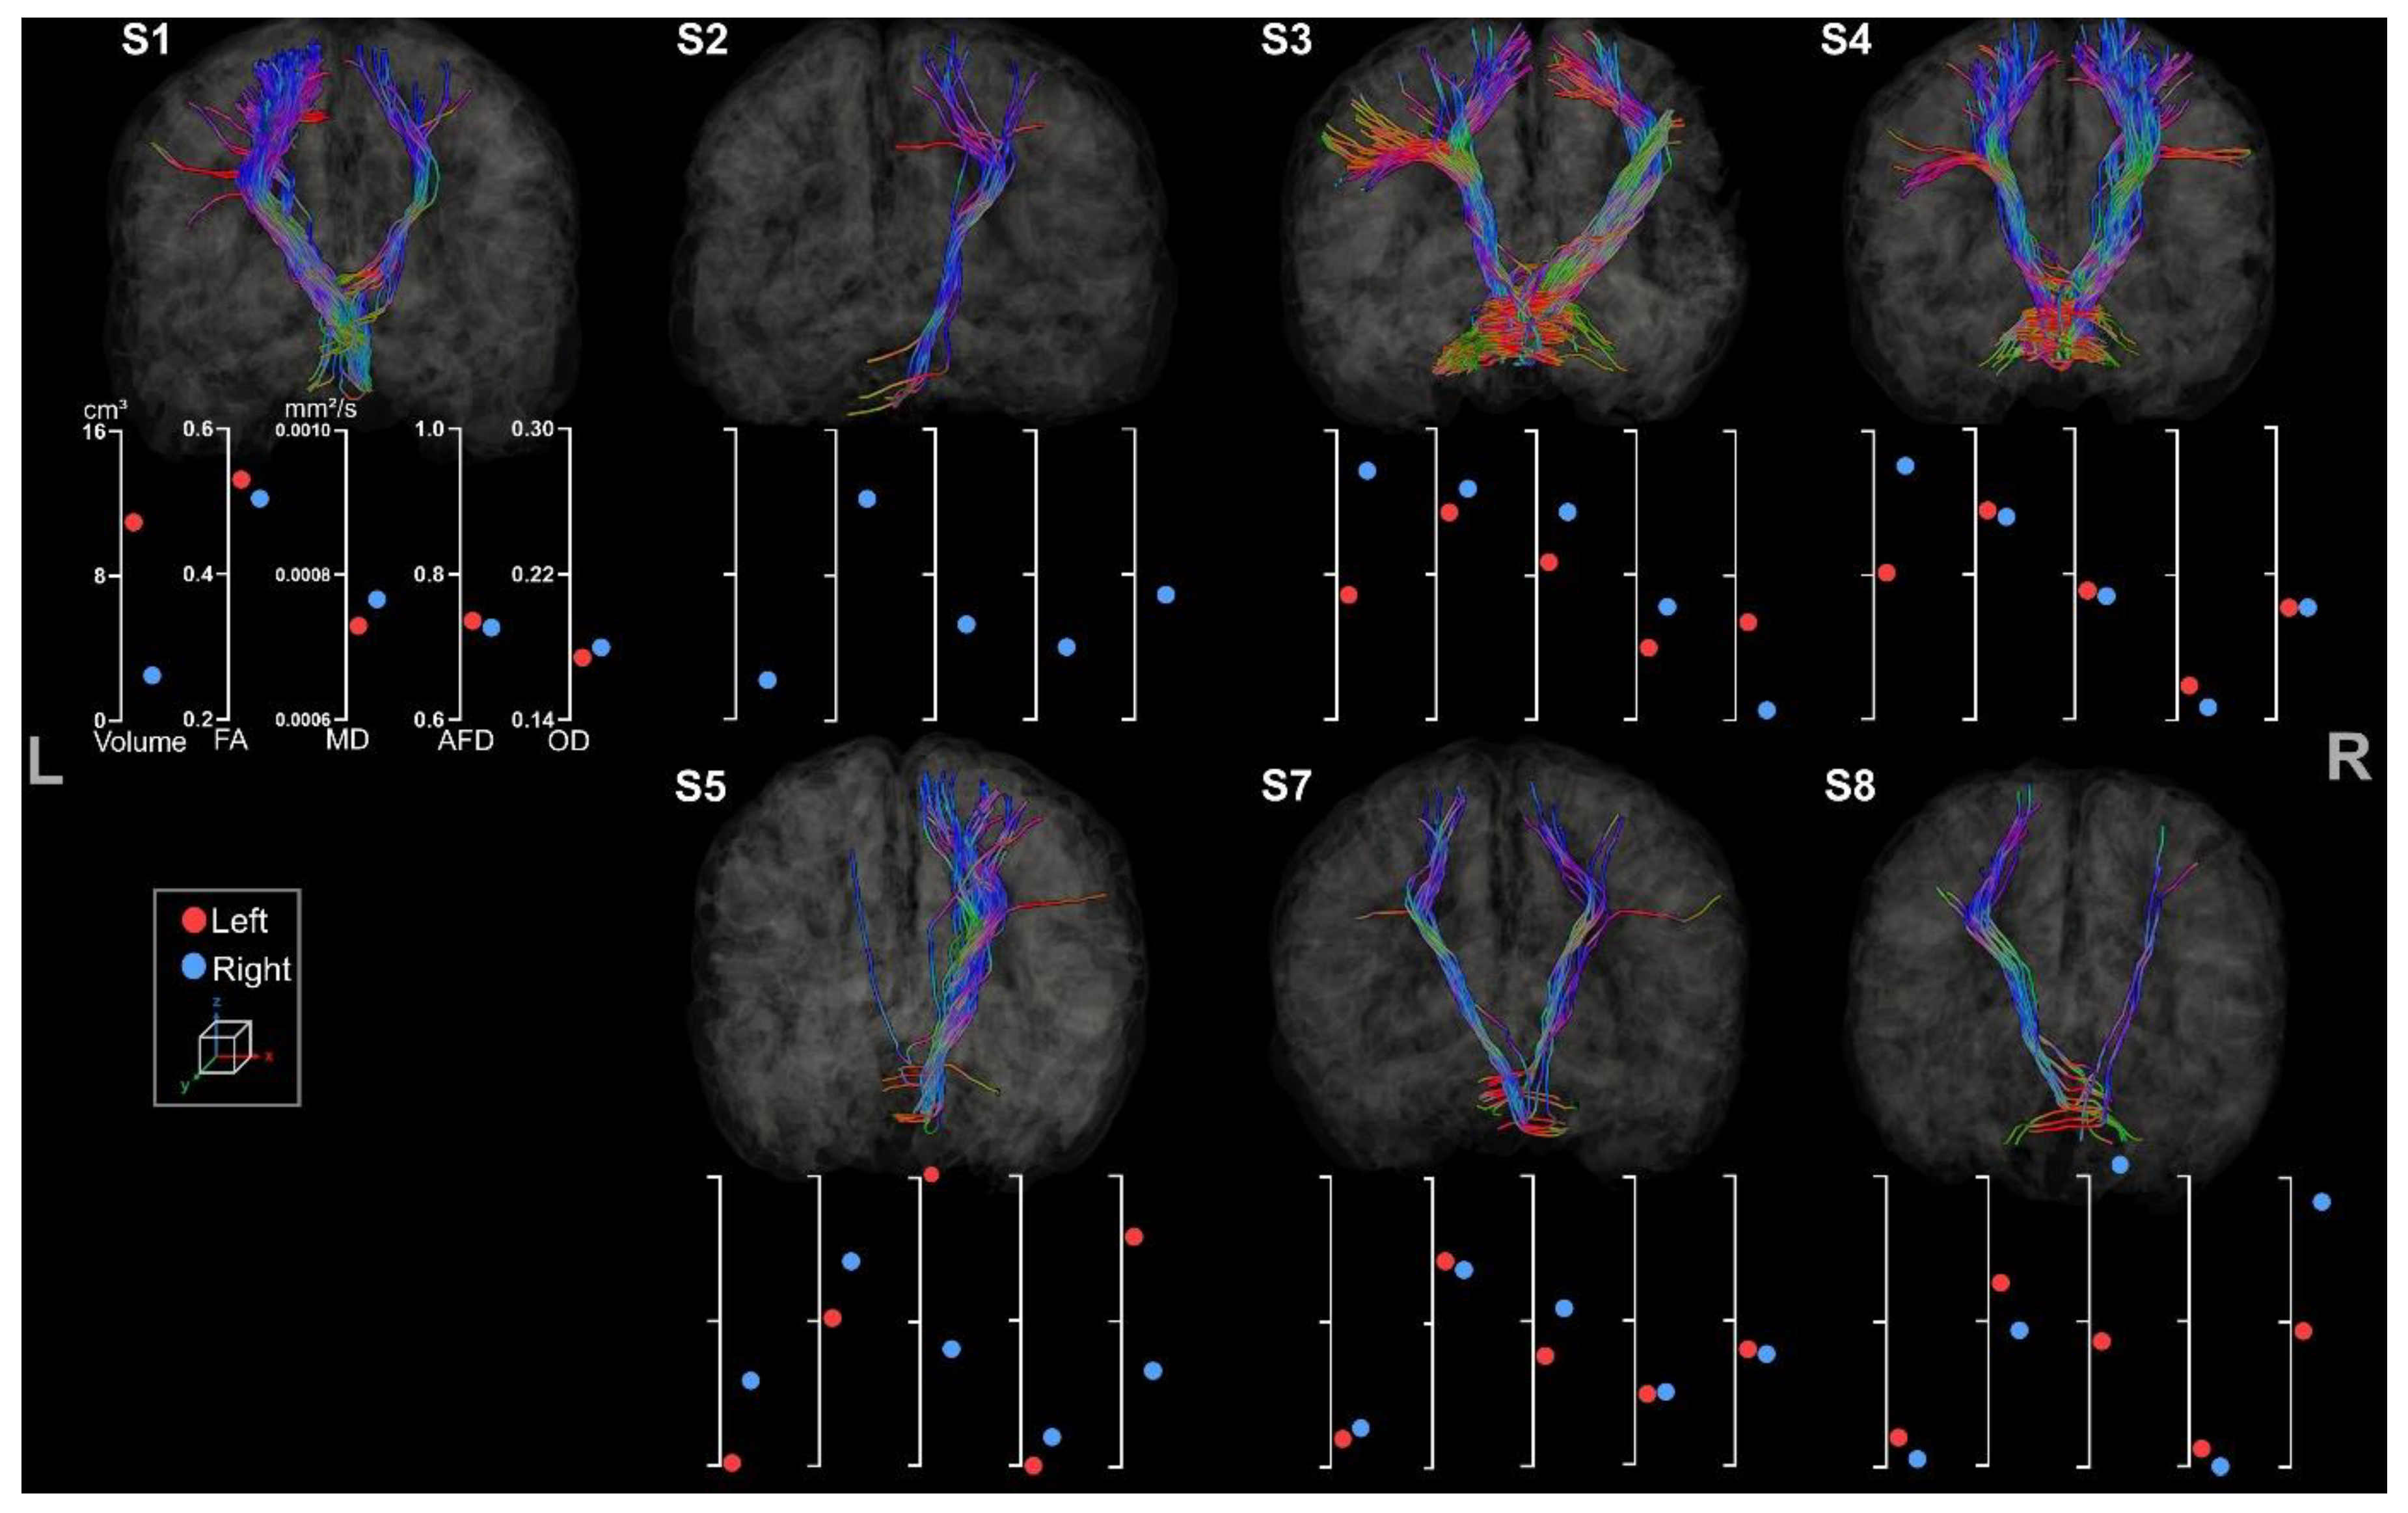

3.2.1. Corticospinal Tracts

3.2.2. Corpus Callosum